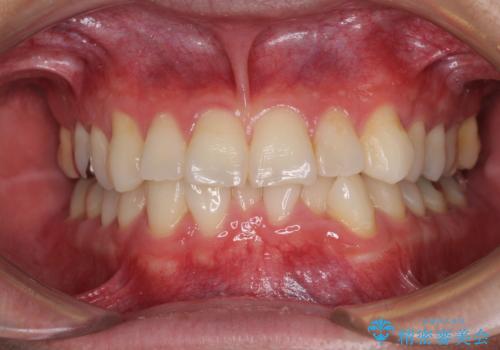

全体のガタガタをインビザラインできれいな歯並びへ